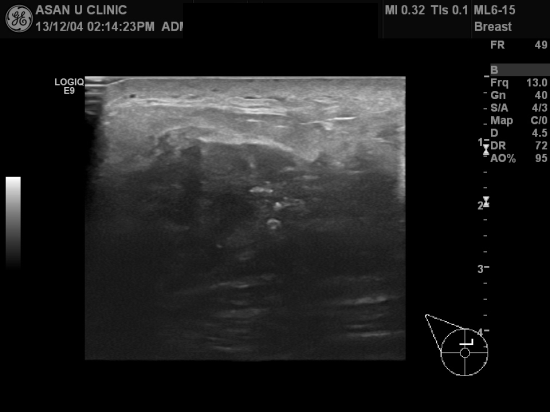

아산유외과 개원 후 43번째 유방암진단.

32세 여성분입니다.

우측유방에 만져지는 멍우리 있어 설마 32세에...라고 생각하시다

건강검진 통해 본원에 의뢰되셨읍니다.

우측 유방과 우측 액와부에 전이의심되는 림프절까지 있으며

본원 조직검사와 세침검사로 침윤성 유방암 및 우측 액와림프절 전이 진단되셨으며

젊은 유방암 클리닉 통해 치료 받고 계십니다.

드물지만 30대도 만져지는 몽우리가 있다면

미루지 말고 검사하세요.